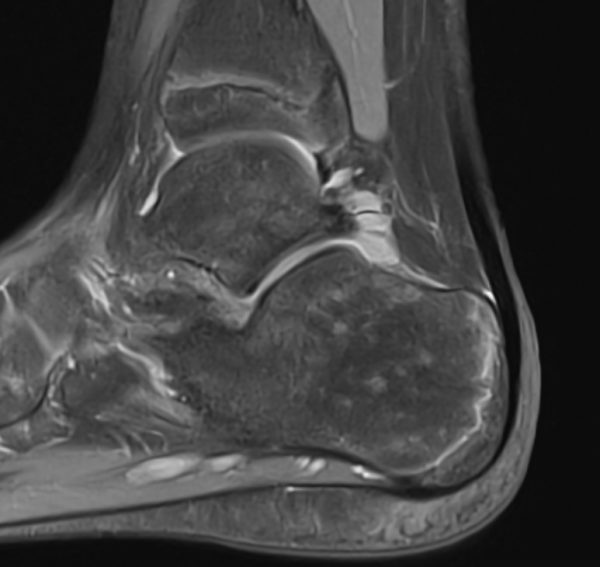

Obwohl die erste Verdachtsdiagnose für den erfahrenen Fußspezialisten einfach zu stellen ist, führen wir in unserer Praxis in Berlin regelmäßig weiterführende Untersuchungen durch. Denn es gibt zwei sehr seltene, aber schwerwiegende Erkrankungen, die sehr ähnliche Beschwerden verursachen können: ein Tumor und die Osteomyelitis (Infektion des Knochens mit Bakterien). Beide Diagnosen dürfen in keinem Fall übersehen werden, da sonst schwerwiegende Folgen für die Patienten entstehen können. Aus diesem Grund führen wir zu Beginn der Therapie ein MRT der Ferse durch. Sind beide Fersen (gleichzeitig oder abwechselnd) betroffen, ist die Wahrscheinlichkeit für Tumor oder Osteomyelitis verschwindend gering – dann kann oft auf weitere Untersuchungen verzichtet werden.

Die Bildgebung mit MRT und / oder DVT kommt also nur zum Ausschluss schwerwiegender alternativer Schmerzursachen zum Einsatz. Daher ist es nicht sinnvoll, Bildgebung mit MRT, DVT oder Röntgen der schmerzfreien Gegenseite zu machen.

In unserer Praxis führen wir bei einseitigen Fersenschmerzen routinemäßig ein MRT durch – nicht um Morbus Sever zu bestätigen, sondern um seltene aber schwerwiegende Differenzialdiagnosen wie einen Knochentumor oder eine Osteomyelitis (Knochenentzündung) zuverlässig auszuschließen. Bei beidseitigen Beschwerden ist die Wahrscheinlichkeit für solche Erkrankungen verschwindend gering; hier kann häufig auf weitere Bildgebung verzichtet werden.